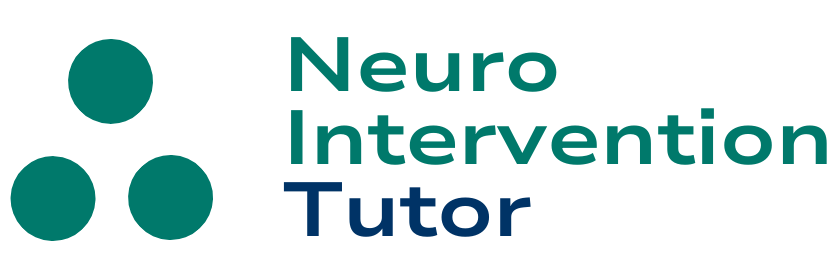

Sometimes we get a glimpse into the world of disease not usually evaluated by cerebral angiography. No doubt, this is a rediscovery of long forgotten facts from pre-cross-sectional era. This 60+ patient came in with mild confusion and amnesia. A CT scan showed hyperdensity in the posterior left hippocamal formation (pink arrows), which was initially interpreted as being in the adjacent perihippocampal cistern, raising the specter of subarachnoid hemorrhage.